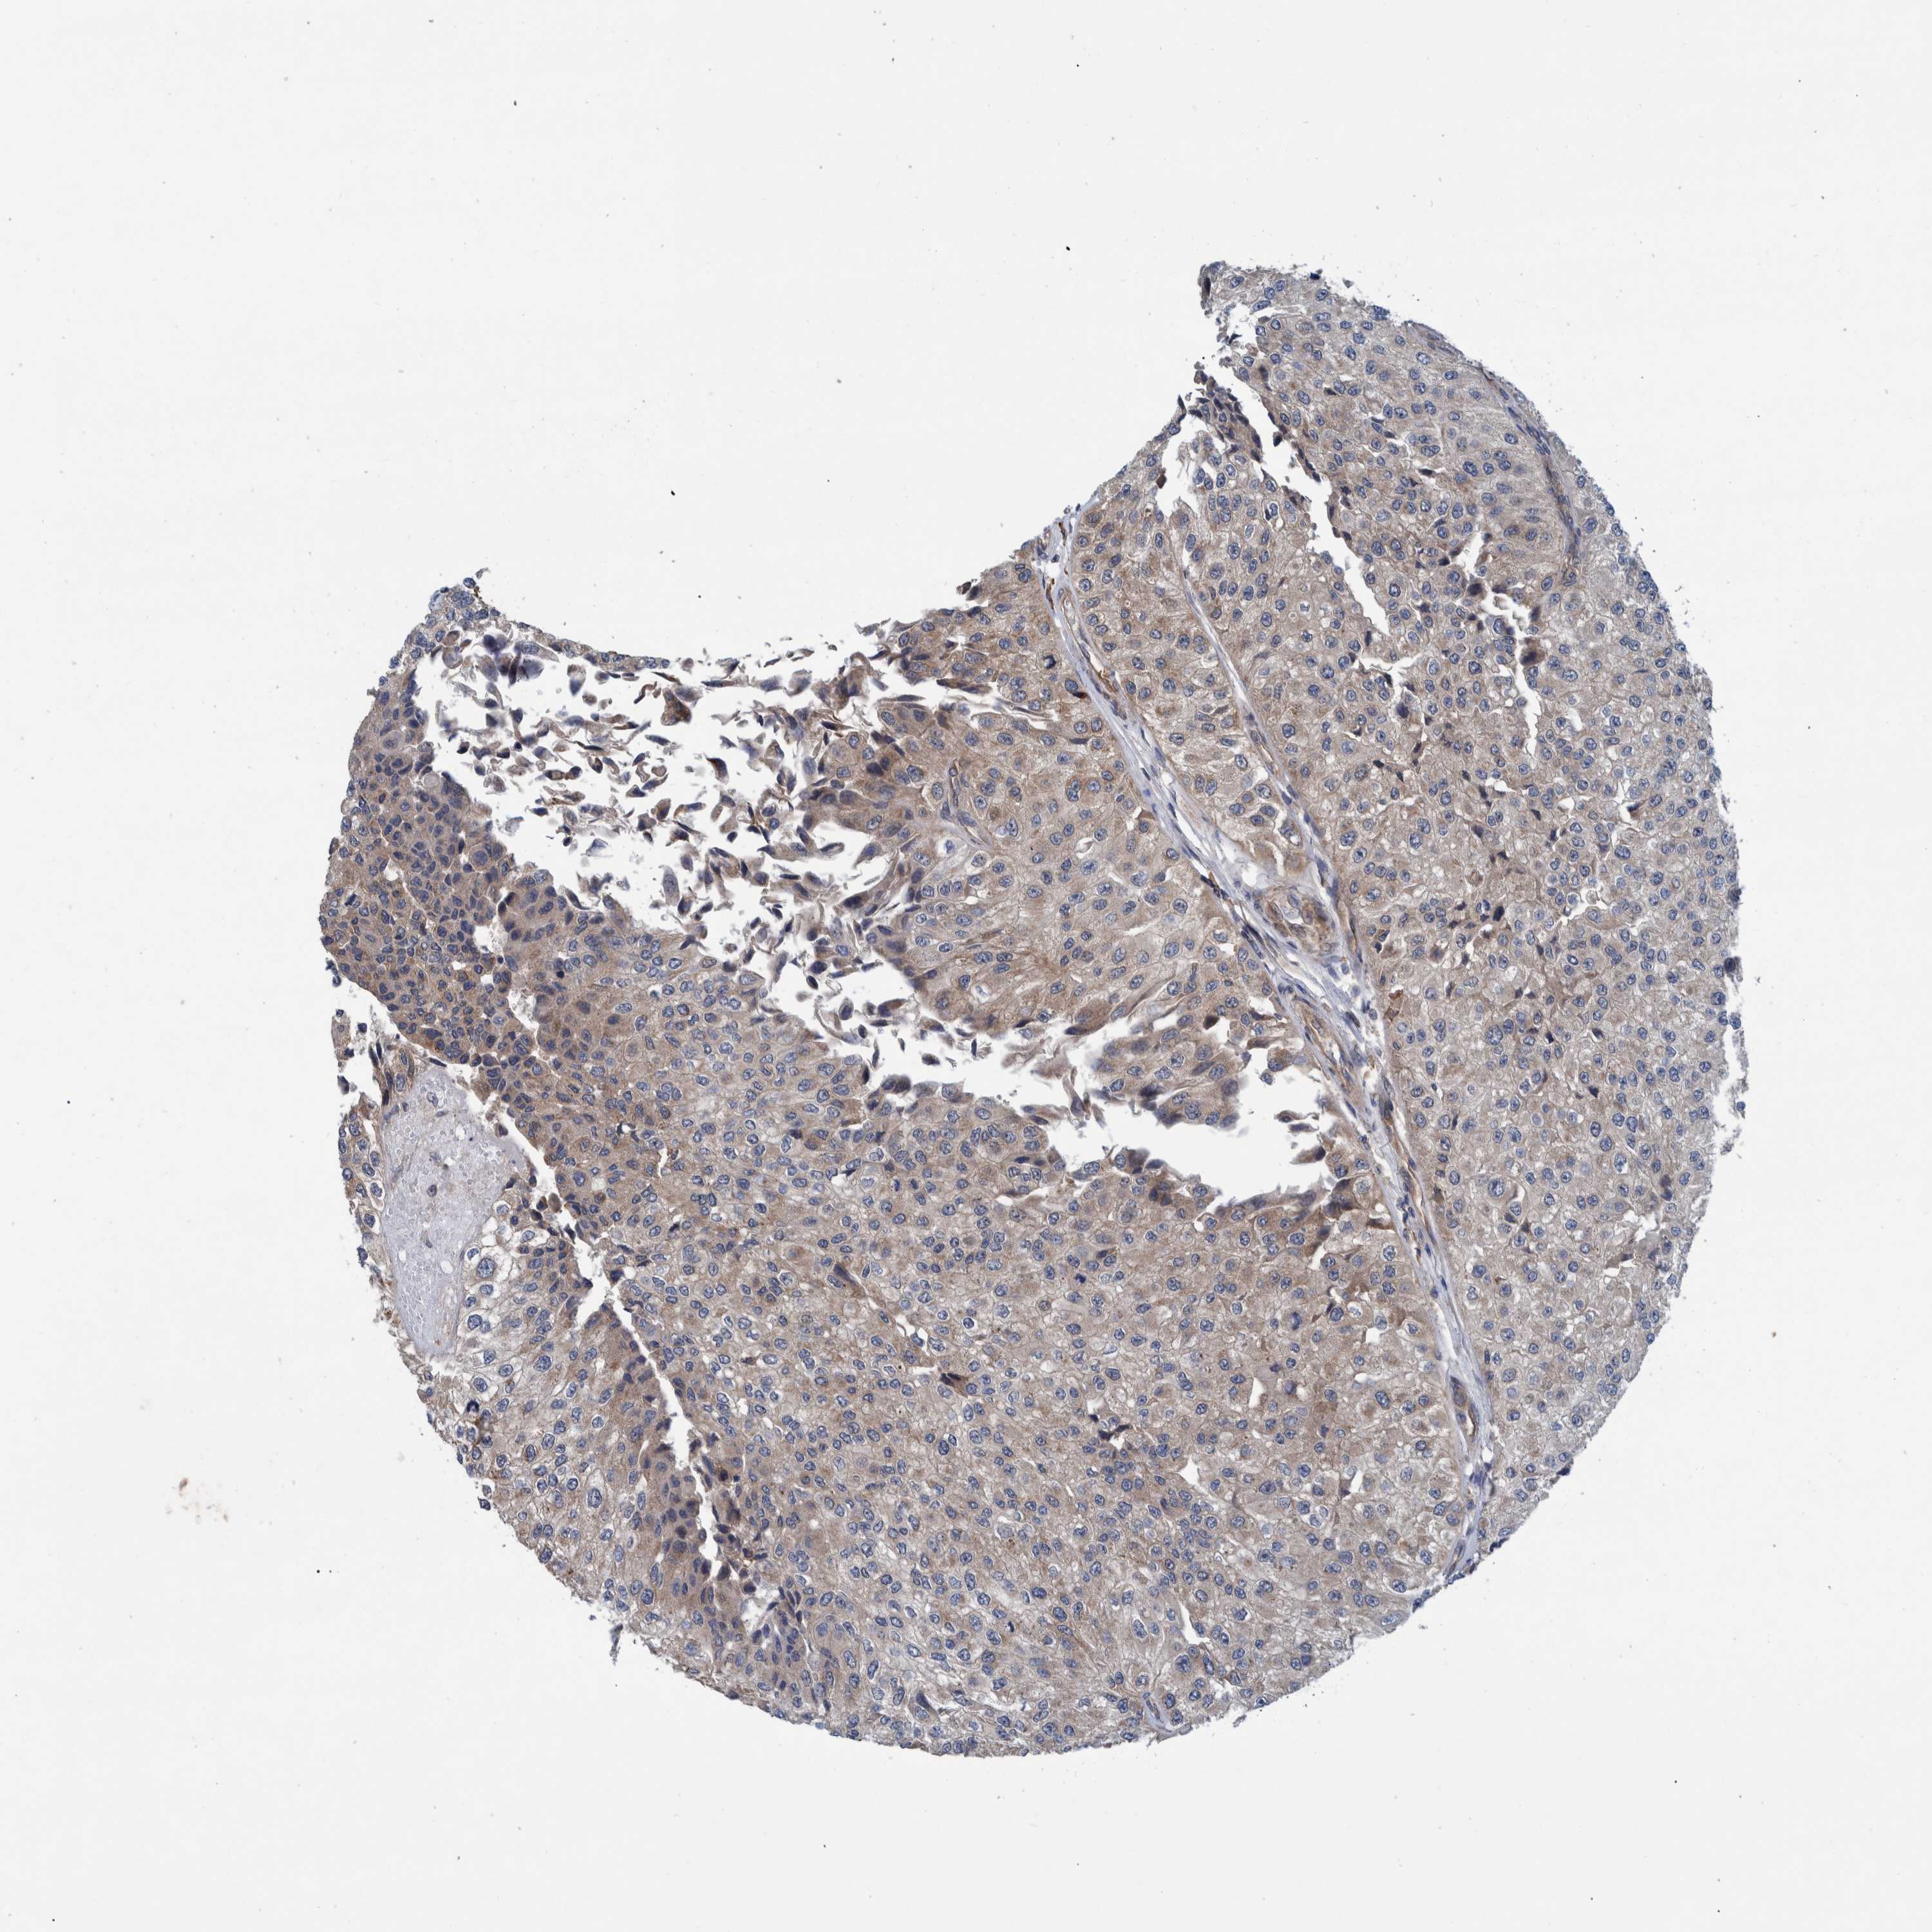

UROTHELIAL CANCER - Protein expressioni

A mouse-over function shows sample information and annotation data. Click on an image to view it in a full screen mode. Samples can be filtered based on level of antibody staining by selecting one or several of the following categories: high, medium, low and not detected. The assay and annotation is described here.

Note that samples used for immunohistochemistry by the Human Protein Atlas do not correspond to samples in the TCGA dataset.

Antibody stainingi

Antibody staining in the annotated cell types in the current human tissue is reported as not detected, low, medium, or high, based on conventional immunohistochemistry profiling in selected tissues. This score is based on the combination of the staining intensity and fraction of stained cells.

Each image is clickable and will lead to virtual microscopy that enables deeper exploration of all samples and also displays staining intensity scores, fraction scores and subcellular localization as well as patient and tissue information for each sample.

Antibody HPA022522

Antibody HPA023007

Staining

High

Medium

Low

Not detected

Intensity

Strong

Moderate

Weak

Negative

Quantity

>75%

75%-25%

<25%

None

Location

Nuclear

Cytoplasmic/membranous

Cytoplasmic/membranous,nuclear

Urothelial carcinoma, Low grade

Urothelial carcinoma, High grade